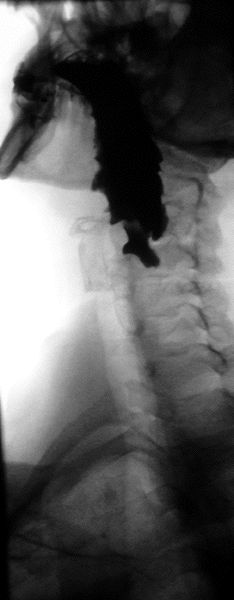

Esofagograma

El esofagograma, también denominado trago de bario, es un estudio de gabinete, que consiste tomar radiografías en varias posiciones para obtener imágenes del esófago, con el fin de determinar alteraciones de la anatomía normal, para lo que el paciente ingiere un medio de contraste opaco a los rayos X (generalmente sulfato de bario diluido en agua, en caso de sospecha de ruptura del tracto se utiliza contraste iodado).